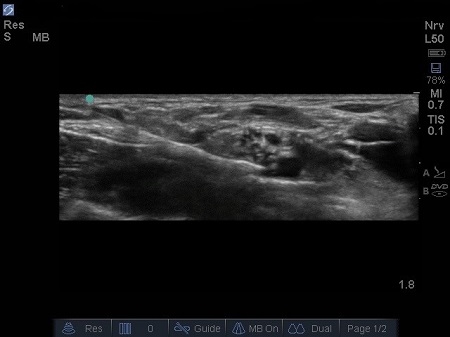

- Local anaesthetic (LA) should spread around the hypoechoic circles causing hydro dissection of the planes. (5) See 6. & 7.

Fig. 6. Initial injection of LA, note proximity to subclavian artery. Excellent needle control is required to safely perform this technique.

Fig. 7. Increasing spread of LAj